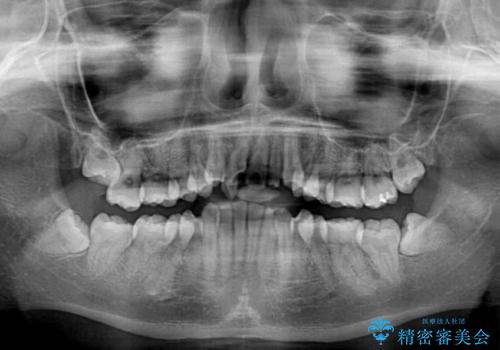

- 上顎の重なっている前歯を気にして来院された患者様です。

重なっている部分は抜歯が必要で、歯の移動量が多く、更には右側にずれている正中を改善する必要がありました。

インビザライン単体での治療は困難と判断し、補助装置により八重歯移動後にインビザラインを用いることとしました。